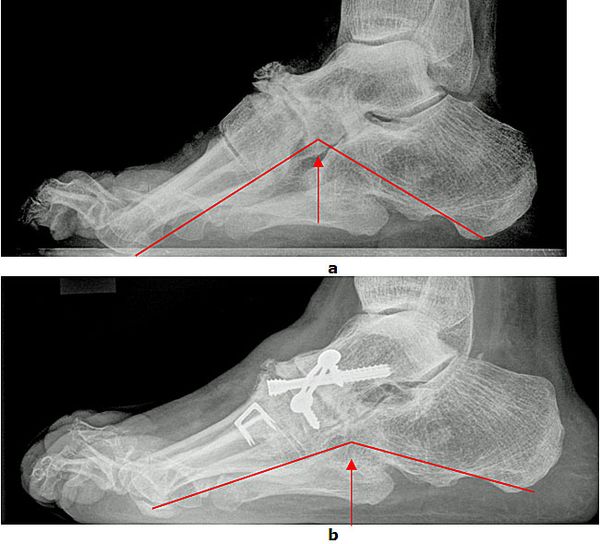

Achsanalyse durch Röntgen Belastungsaufnahmen

In der Röntgendiagnostik werden Belastungsaufnahmen des Fußes zur Bestimmung der Achsverhältnisse durchgeführt. Entscheidend ist das Verhältnis zwischen dem ersten Mittelfußknochen und dem Sprungbein sowie der Öffnungswinkel zwischen Fersenbein und Sprungbein. Die Winkel sind beim Plattfuß vergrößert. Außerdem wird der Gelenkzustand beurteilt.

Abb.3: a Absenkung des Längsgewölbes im Röntgenbild. Krankhafte Veränderung der Knochenachsen. b Durch eine gelenkerhaltende Operationsmethode (Verlängerung des Fersenbeins (Evans Osteotomie, Calcaneus Verlängerungs Osteotomie) konnte der Fuß wieder aufgerichtet werden.